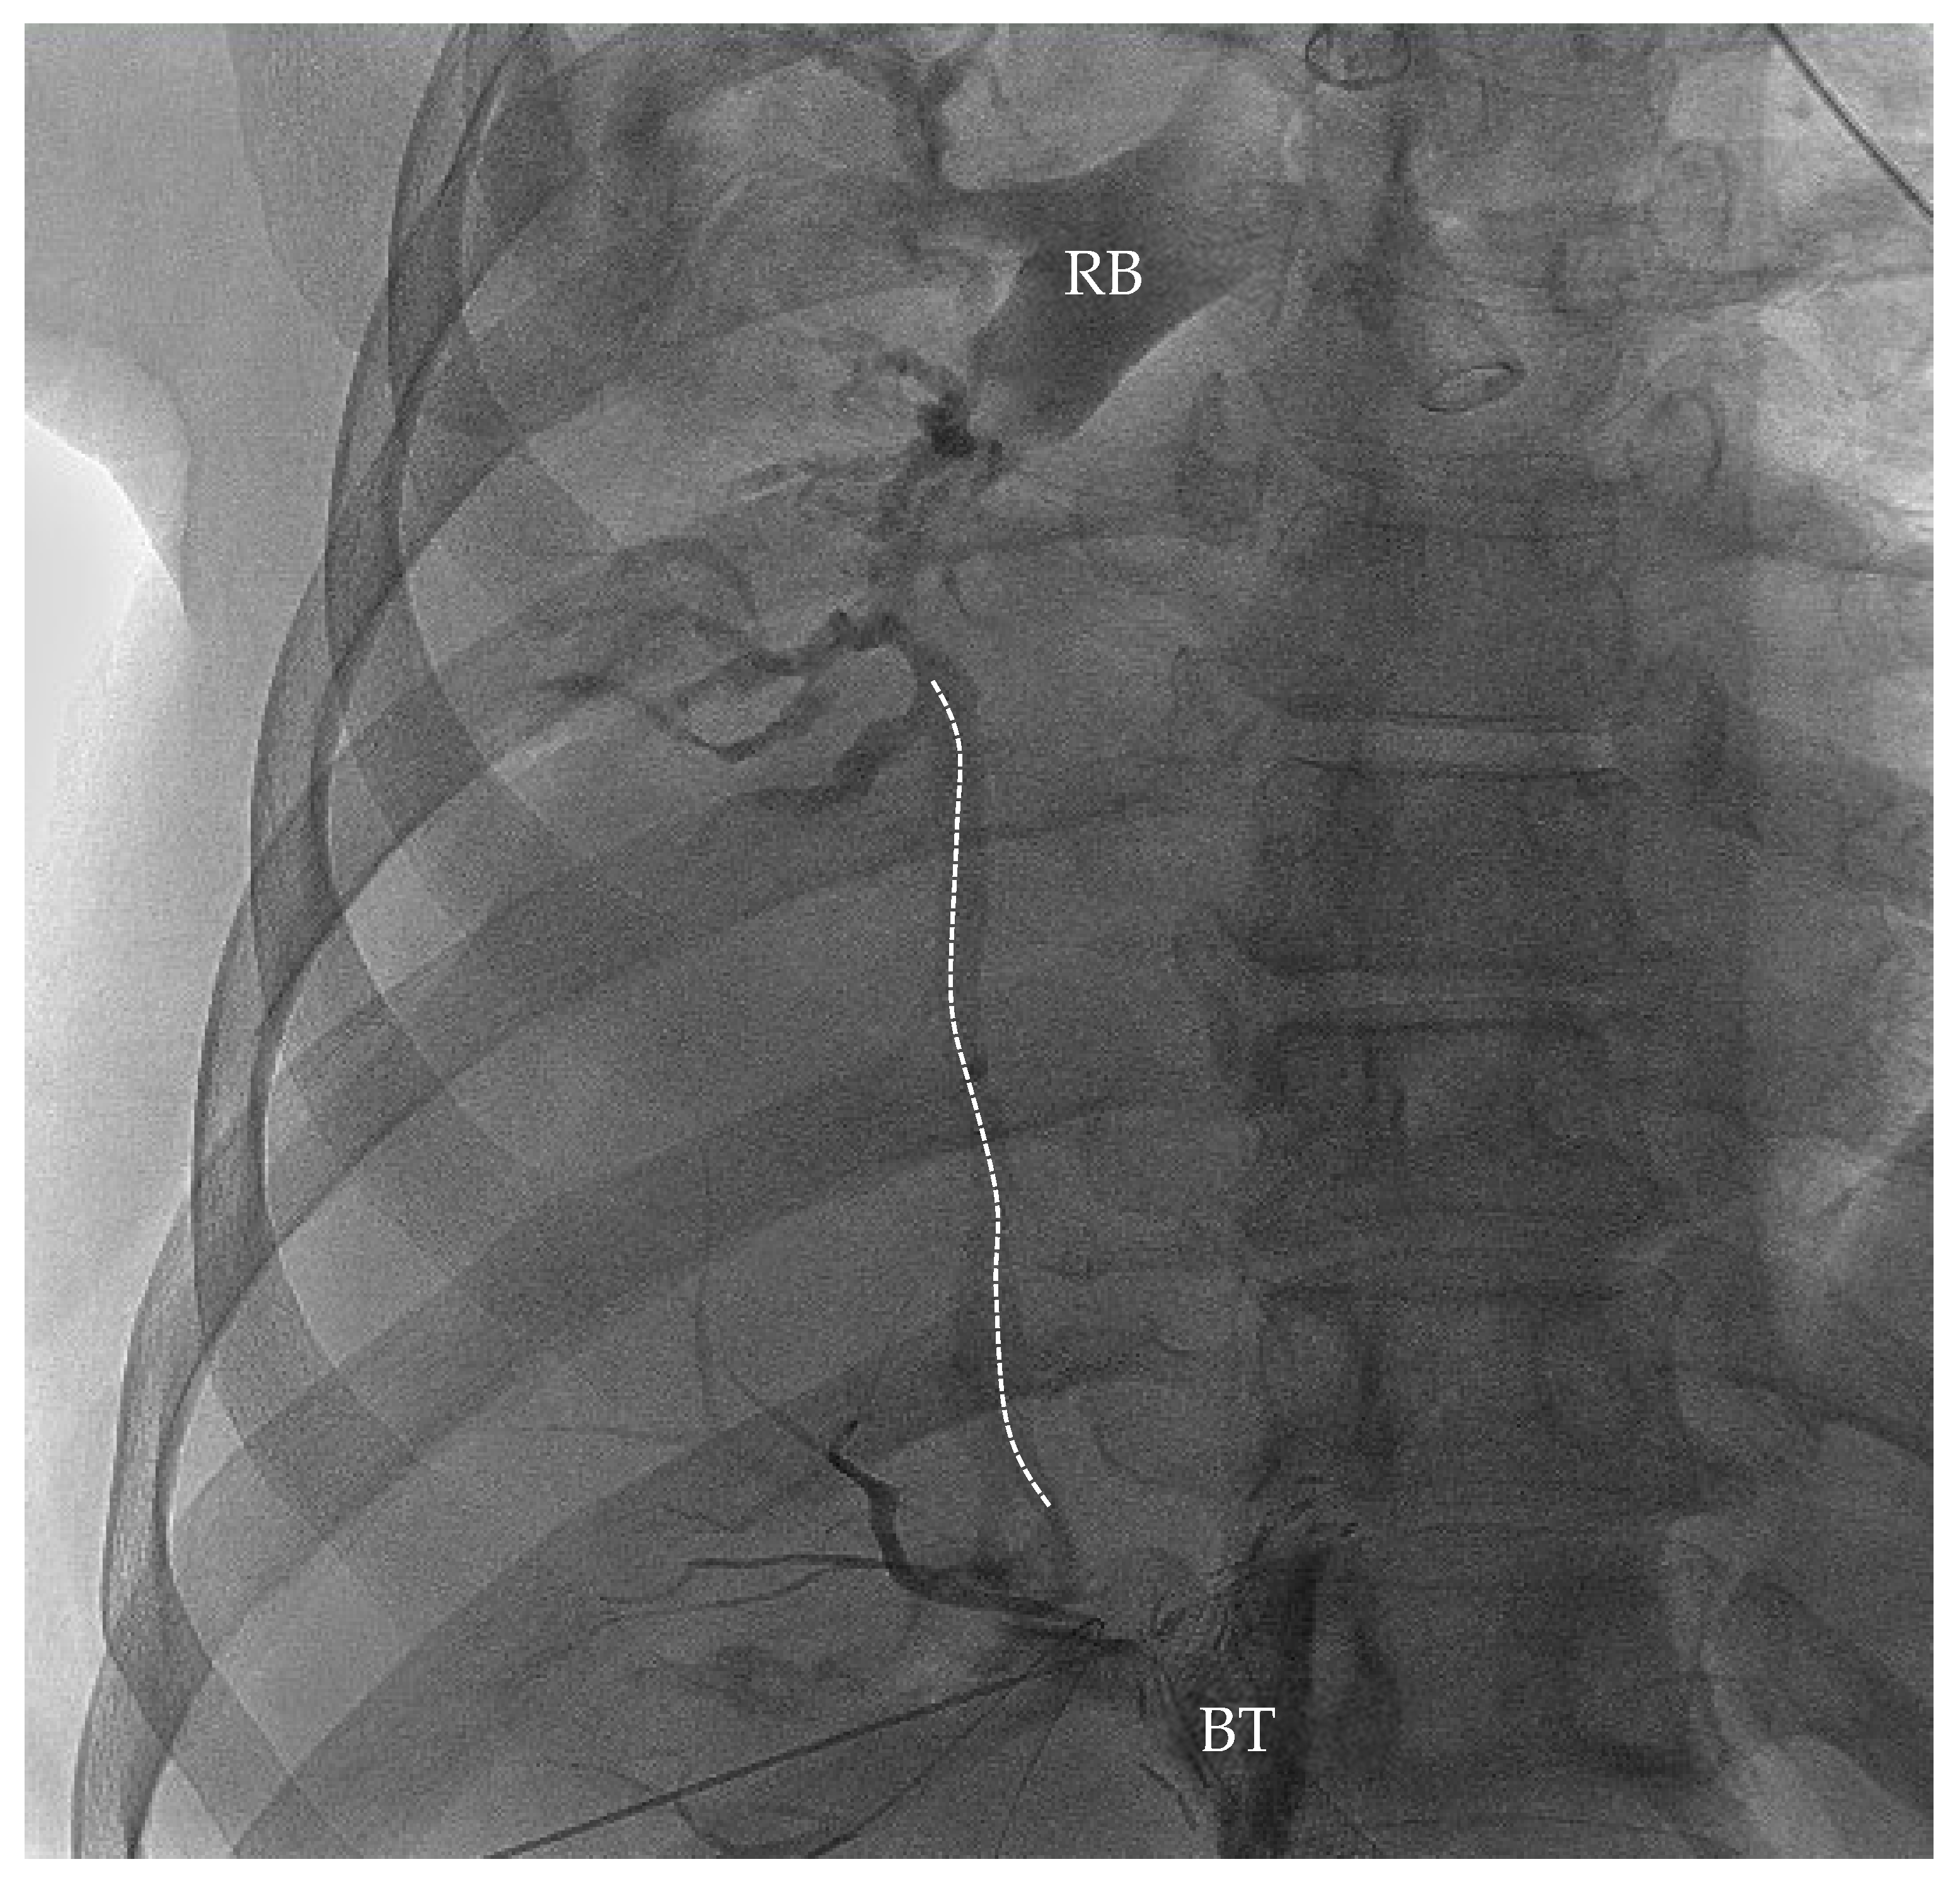

Figure 1. AP contrast fluoroscopy demonstrating BBF post-intubation with DLT in the IR suite. The dashed line tracks the fistula between the biliary tree and the right airway. Contrast clearly demonstrates a tract between the biliary tree and the right bronchus through the BBF. RB = right bronchus; BT = biliary tree.

Emergent biliary drain placement with interventional radiology (IR) was performed. The patient remained stable on single-lung ventilation. The IR team noted a biliary pleural fistula (T + 180 min) with connection to the right airway (see Figure 1). During the procedure, more bilious and bloody secretions were suctioned out of the right lung by DLT. Mean arterial pressure was greater than 65 mmHg during the entirety of the procedure. Pressure support of 15 cmH2O provided adequate ventilation with O2 saturation > 99% during the entirety of the procedure with an average tidal volume of 250 mL. At the end of the procedure, the patient was admitted to the medical intensive care unit (MICU) with the DLT on single-lung ventilation with phenylephrine and propofol on the intravenous line. The external biliary drain had significant bloody and bilious drainage to gravity.